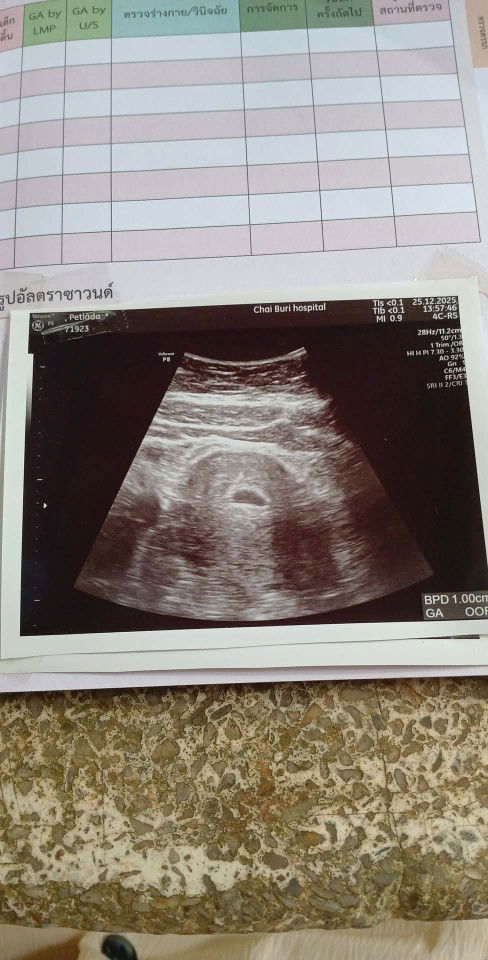

จากเมื่อวานที่ได้หาหมอ เพราะอาการเลือดออกที่ช่องคลอดเป็นสีน้ำตาลไม่เยอะมากมีอาการปวดท้องน้อยร่วมด้วยเหมือนมีอะไรแทงที่มดลุก หมออัลต้าซาวบอกว่าถุงตั้งครรภ์ยังอยุ่ดีที่มีเลือดออกเพราะมดลุกขยาย วันนี้ที่ 16 ได้มาโรงบาลอีกรอบเพราะอาการเดิมแต่ปวดมากกว่าเดิมและมีเลือดสีสดออกมากกว่าเดิมออกเหมือนประจำเดือนมา หมออัลต้าซาวให้และตรวจภายในผลสรุปคือแท้ง หมอเวรวันนี้เลยถามหาหมอที่เข้าเวรตรวจเมื่อวานว่าทำไมถึงไม่ให้แอดมิดตั้งแต่เมื่อวานขี้เกียจหรืออะไรกันตั้งครรภ์อายุครรภ์แค่7สัปดาห์มันเสี่ยงมาก เราเลยอยากบอกแม่ๆทุกท่านเพื่อเป็นอุทาหร หมอไม่ได้ห่วงคนไข้ทุกคนเสมอไป เราเสียใจมากที่เลือกโรงบาลผิดตั้งใจมากกลับลุกคนนี้เพราะมีลุกยากอายุ 41 โอกาสมีก็น้อย#ขอบคุณสำหรับคอมเม้นล่วงหน้าค่ะ